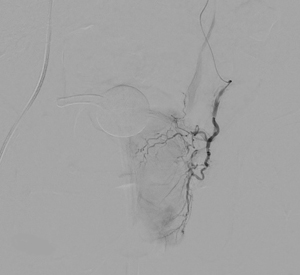

picture 2Overall, the procedure involves shrinking the prostate by treating its blood vessels. An interventional radiologist gains access through a small incision in the upper thigh or the wrist. From there, small particles are injected into the prostate to slow the blood flow to the gland, causing the prostate to shrink. Relief from BPH symptoms occurs in the following weeks and months. It is a relatively painless procedure using conscious sedation. After the procedure, UCSF Radiology follows up with patients at one, six and 12 months.